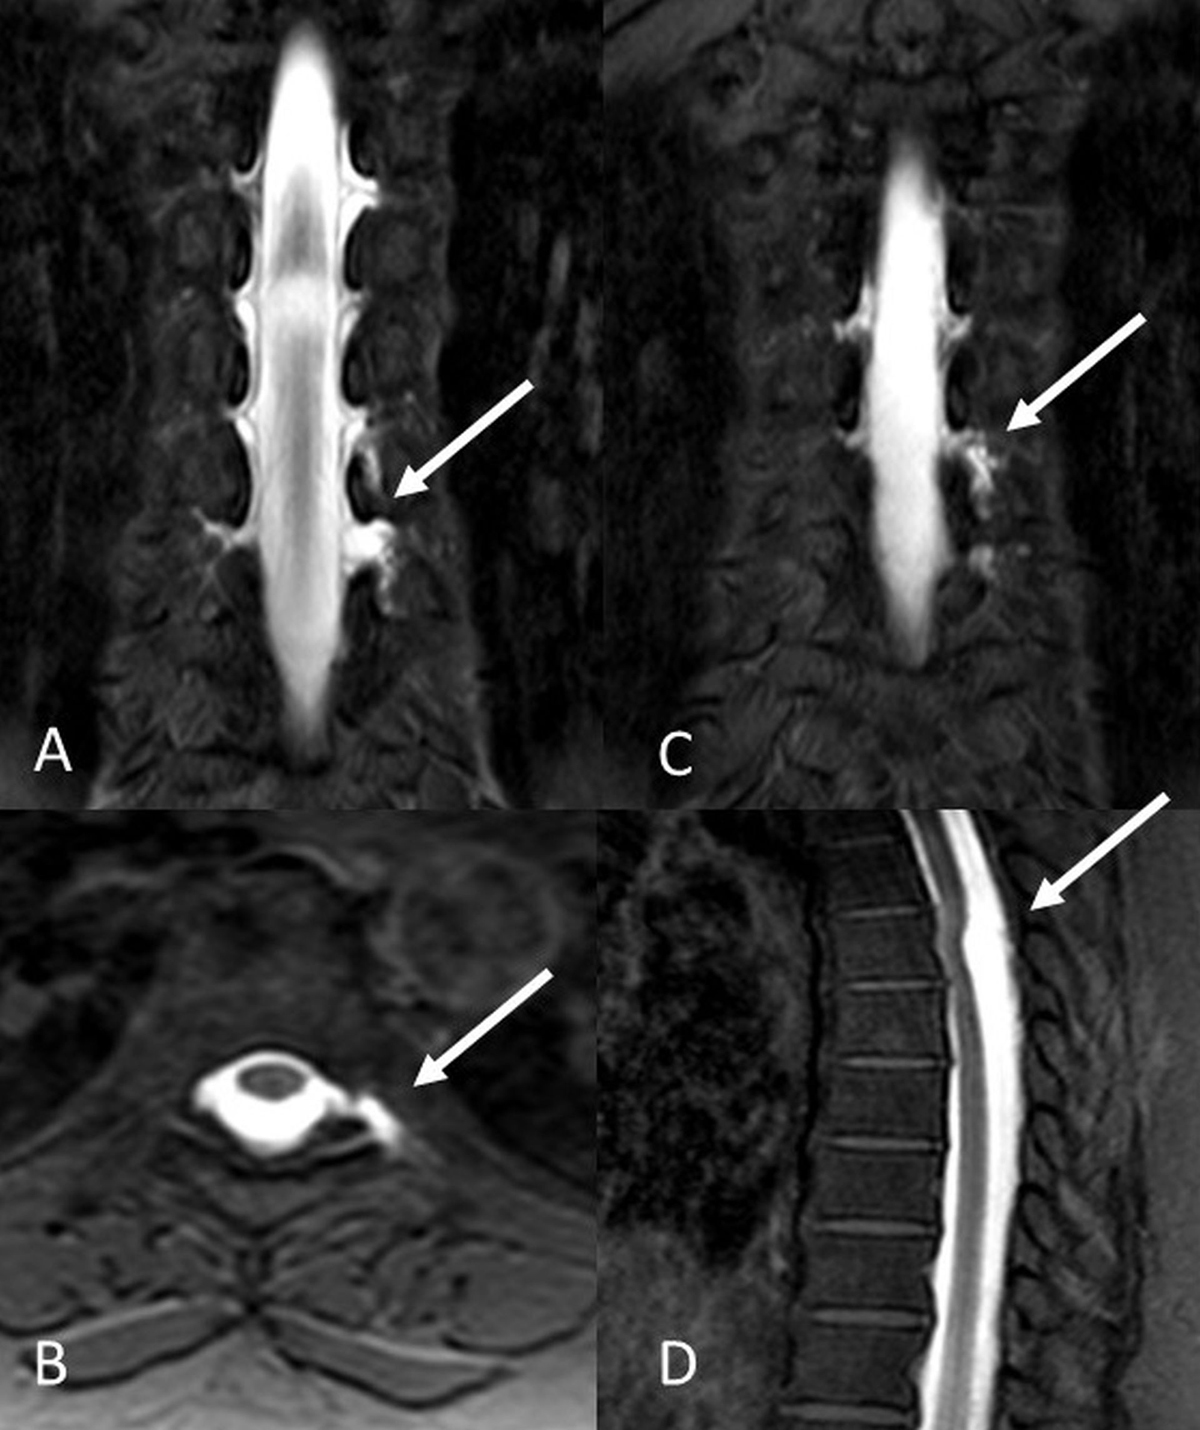

Treatment in SIH patients includes conservative therapy, epidural blood patch and surgical repair of dura in resistant CSF leaks. In our patients, 13 of 18 CSF leaks were treated with epidural blood patch. In a 52 year-old female patient with CSF leak at C2 level, multiple site epidural blood patch was applied through a single lumbar entry with a microcatheter. Thirty ml autologous blood introduced to cervical epidural areas. Control Gd-MRM images revealed significant decrease in CSF leakage and complaints of the patient resolved (Figure 2).

Figure 2

Intrathecal Gd-MRM images in a 47-year-old female patient demonstrated CSF leak at T6–T8 levels. T1W-SPIR coronal (A, B), and axial (C) images revealed diverticular pouching and CSF leakage. A cystic lesion posterior to spinal cord was revealed in T1W-SPIR sagittal images (D).